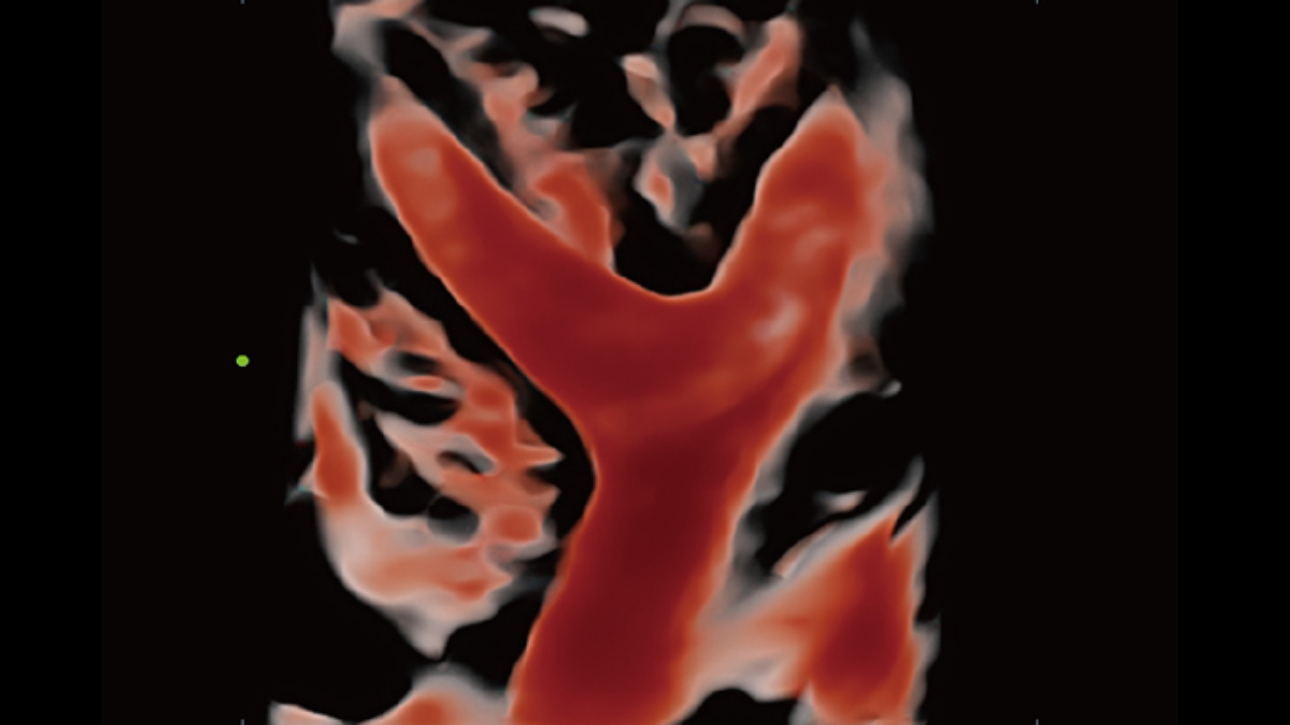

By transmitting and receiving a relatively smaller number of large zones, Advanced Acoustic Acquisition extracts more information from each acquisition, 10 times faster than a conventional line-by-line beamforming method.